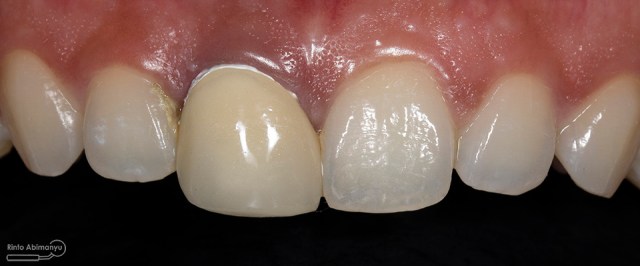

Begini hasil akhir setelah sementasi crown…

Foto klinis setelah pemasangan crown

Alhamdulillah pasien nya senang sekali…. dia puas dan saya pun senang karena dapat memenuhi keinginan pasien…..